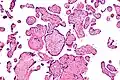

| Micrograph of villitis of unknown etiology. H&E stain. | |

Histomorphologically, VUE is characterized by a lymphocytic infiltrate of the chorionic villi without a demonstrable cause. Plasma cells should be absent; the presence of plasma cells suggests an infective etiology, e.g. CMV infection.